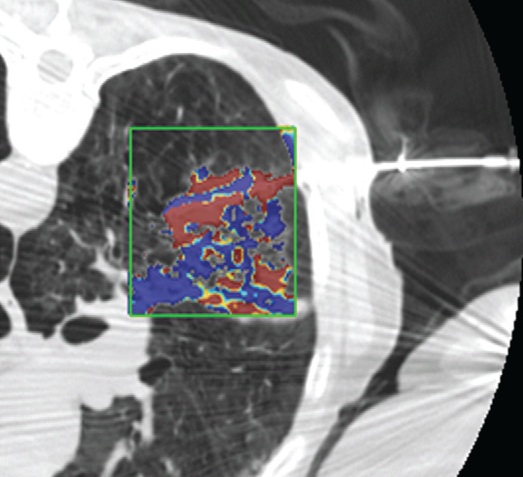

影像也可以测量组织温度;这些技术可以帮助热消融和确保肿瘤可以完全治疗而不损伤邻近重要脏器【110】。因为不同的组织有不同的死亡阈值,了解被释放的热计量甚至可能会促进某些选择性组织破坏【111】。MR测温已经被开发用于高能聚焦超声的应用【112,113】,但也可以应用于其它消融模式,如射频、激光、微波和热盐水【114,120】。通过检测磁共振质子成像与温度相关的频率变化,可以测量组织温度在1°C以内的变化【121】,因为维持将近54°C或更高温度超过1秒,被认为可以导致细胞死亡【122】,MRI的温度测量能够提供可量化的、评价热消融完整性的无创方法。而其它一些温度敏感MRI技术,如质子密度、T1和T2弛豫时间,磁化传递( magnetization transfer)和扩散也被应用,质子共振频率变化更常应用于临床。MRI温度测量的局限性依然存在,包括运动伪影,消融工具或脂肪环境导致的磁场不均匀性以及有限的瞬时清晰度(temporal resolution)。 虽然到目前为止,很多技术在临床实践中尚未发展成熟,CT和超声已经被建议未来作为测量组织温度无创方法。CT值和声速(sound velocity)都与温度变化相关【123,124】。 Intraprocedural monitoring. CT thermometry during percutaneous radiofrequency ablation of lung cancer. Changes in CT attenuation may be used to approximate the temperature.